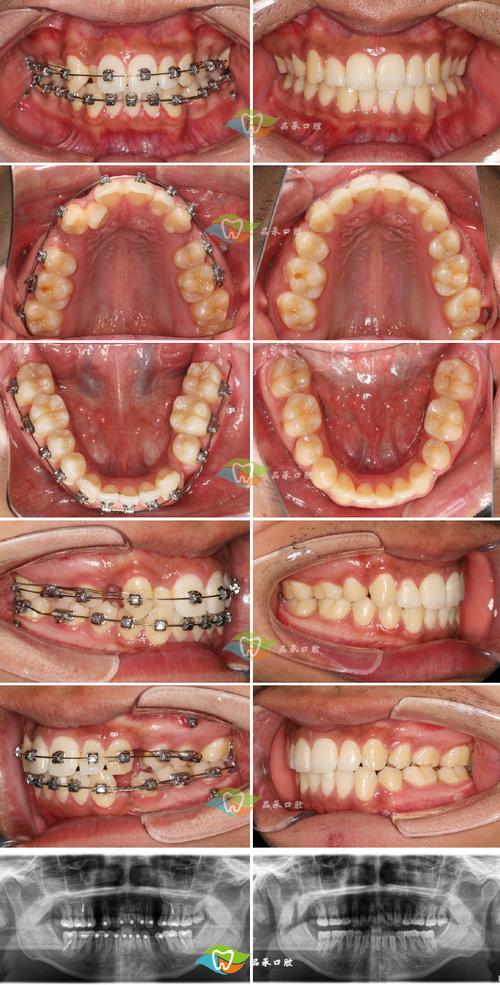

拔牙矫正作为一种常见的牙齿矫正方式,主要针对牙齿拥挤、前突、颌骨发育异常等问题,通过拔除部分牙齿为剩余牙齿创造移动空间,从而达到排列整齐、咬合协调的目的,许多患者在接受矫正前都会有一个核心担忧:拔牙矫正后的牙齿会不会反弹?这一问题涉及到矫正原理、术后维护、个体差异等多方面因素,需要从科学角度进行详细解析。

牙齿矫正的本质是利用外力(如矫治器)使牙齿在牙槽骨中缓慢移动,移动过程中牙槽骨会发生改建(一侧吸收、一侧增生),最终达到新的位置,矫正结束后,牙齿周围的牙槽骨和牙周组织需要时间稳定,而牙齿本身也有回到原始位置的“记忆性”,因此反弹是牙齿矫正后可能存在的风险,但并非必然发生,临床数据显示,若患者严格遵守医嘱进行保持和维护,大部分拔牙矫正 cases 可以长期稳定;反之,若维护不当,反弹风险会显著增加。